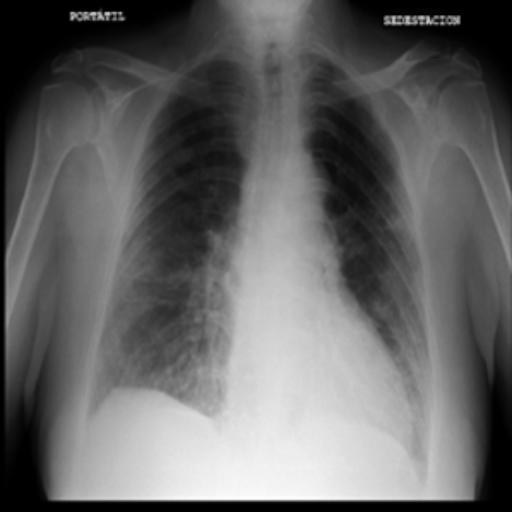

The dataset chosen in this paper is an open-source dataset, the dataset is selected from the open-source database, the database contains 150 lung X-ray images and their corresponding 150 masks, and we select four of them for presentation, the results are shown as follows, the four images in the first row are the original images of the lung X-ray, and the images in the second row in the corresponding position are their corresponding masks, as shown in Fig. 1.

Figure 1. Partial data.